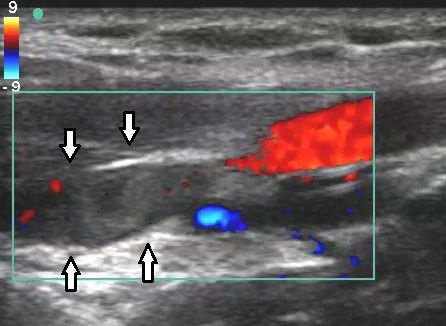

The scan combines two types of ultrasound. One creates clear images of your veins and arteries, while the other (Doppler) shows the speed and direction of blood flow. Together, this provides detailed, real-time information that allows your consultant to make an accurate diagnosis and plan the most appropriate treatment.

Varicose veins are often caused by faulty valves within the veins, leading to blood flowing in the wrong direction (known as venous reflux). These underlying problems cannot always be seen by looking at the veins on the surface of the skin alone.

Duplex scanning allows your consultant to see exactly which veins are affected, where the reflux is coming from, and how severe it is. This information is essential for choosing the most effective treatment and avoiding unnecessary or ineffective procedures.